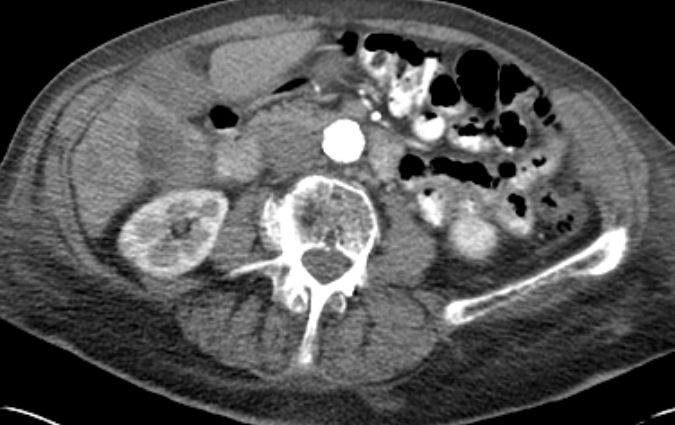

86-jähriger Mann, bei dem vor 9 Monaten eine Cholezystektomie wegen gedeckt perforierter Cholezystitis vorgenommen wurde. Jetzt Verdacht auf Leberabszess. Die laparoskopische Biopsie ergab ein Adenokarzinom. Die Nachbefundung der Gallenblase erbrachte immunhistochemisch den Nachweis eines Gallenblasenkarzinoms. | ||

Lebermetastase |